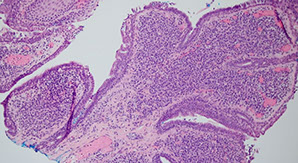

Syringocystadenoma Papilliferum (SCAP)

aka papillary syringadenoma

b9 sweat gland proliferation that arises in the middle of a nevus sebaceus

- warty tumor of scalp, neck, and face that can occur at any age

- clinically is a slow growing or recent change in a brithmark, may be crusty and start to bleed

- 1/3 have adjacent nevus sebaceus, 10% with adjacent BCC

- malignant counterpart is syringocystadenocarcinoma papilliferum

Micro: glandular papillary prolif connected to skin surface

- has ducts that look similar to sweat ducts sometimes, which are lined by cuboidal cells, that eventually empty to skin surface

- dense plasma cell infiltrate in the dermis, or in the middle of the papillary structures